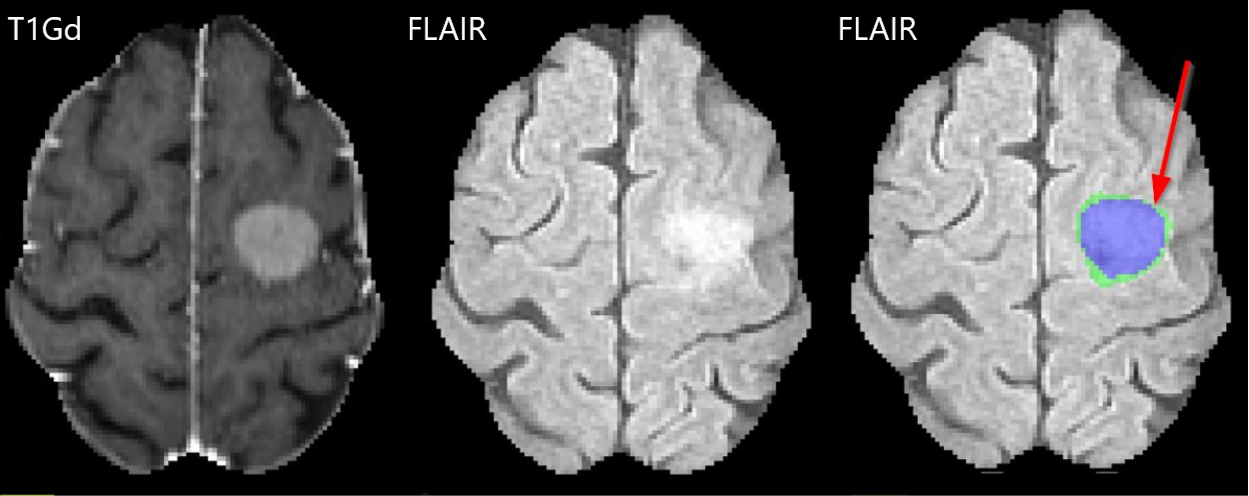

Based on this prior work and others, the BraTS 2023 meningioma challenge defines 3 distinct and non-overlapping segmentation labels (Fig. 3). These include “enhancing tumor”, “nonenhancing tumor core”, and surrounding non-enhancing T2/FLAIR hyperintensity (SNFH). The enhancing tumor label includes all contrast enhancing meningioma, focally thickened meninges (including dural tail), as well as en-plaque meningiomas. This label approximates the region of active, viable tumor. The non-enhancing tumor core label includes all calcification, hyperostosis, necrosis, degeneration, and any other atypical non-enhancing tumor radiographic findings. This label along with the enhancing tumor label (together comprising the “tumor core”) approximately corresponds to the portion of tumor related imaging abnormality that would typically be removed in a gross total resection. The SNFH label includes the entire extent of tumor related T2/FLAIR hyperintensity surrounding the tumor core. This label is distinct from the other labels in that it is composed entirely of brain parenchyma and is not expected to contain any tumor cells, but rather represents irritated, inflamed, and/or edematous brain tissue resulting from adjacent tumor. Importantly, non-tumor related T2/FLAIR signal abnormality, commonly related to chronic microvascular ischemic white matter changes (e.g. leukoaraiosis) or other vascular pathology, was not included in the SNFH label.